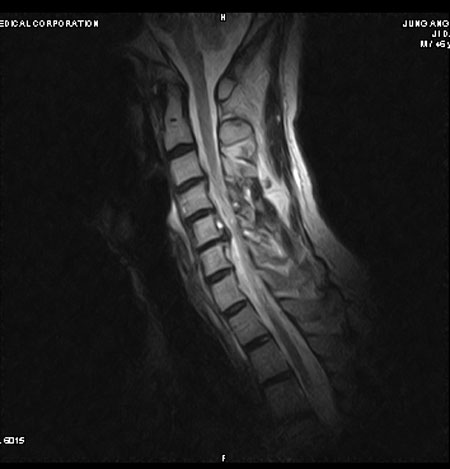

, ü Ư Ű 177 Cm ü 65 Kg 48 ȯ 6C.ڸ , 6C. κ Ḳ , 6C.ھ Ḳ , 6C.ڻ , ()ũ( ߰Ż), ũ(߰Ż)ġ, հ , ġ, , Ḳ ġ ͳ ˻ڷ õ Ḧ Ҵ ũ Խϴ. κа , ؼ ġῡ ɱ ϰ ϴ |